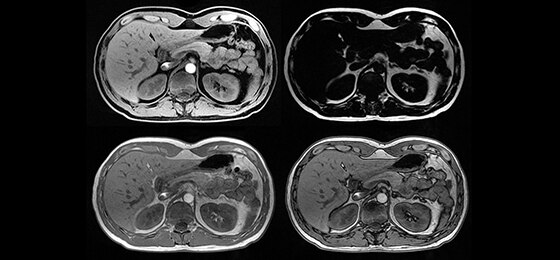

Its full 3.0T magnet and 70 cm bore work together to generate extraordinary image quality without compromises. The result for clinicians is new levels of diagnostic performance.

A large usable field of view is needed to properly image off-center anatomy such as a shoulder or hip. So the Discovery* MR750w features a 70 cm flared, open bore design with a large 50 x 50 x 50 cm field of view.

Intuitive applications help clinicians utilize the full potential of 3.0T MR imaging.

GEM Anterior Array - A lightweight, flexible, thin and pre-formed array to embrace patients’ various sizes and shapes. With 54 cm of S/I coverage, the anterior array permits upper abdominal and pelvic imaging without repositioning the patient and supports parallel imaging in all 3 planes.